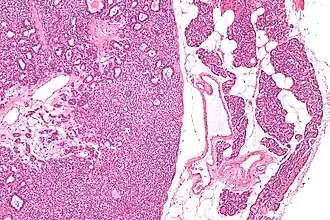

Микропрепарат: аденома паращитовидной железы слева, справа — неизменённая ткань паращитовидной железы. | |

Микропрепарат аденомы паращитовидной железы.

Микропрепарат аденомы паращитовидной железы. Микропрепарат аденомы паращитовидной железы.

Микропрепарат аденомы паращитовидной железы..jpg) Микропрепарат аденомы паращитовидной железы.

Микропрепарат аденомы паращитовидной железы..jpg) Микропрепарат аденомы паращитовидной железы.

Микропрепарат аденомы паращитовидной железы..jpg) Микропрепарат аденомы паращитовидной железы.

Микропрепарат аденомы паращитовидной железы.